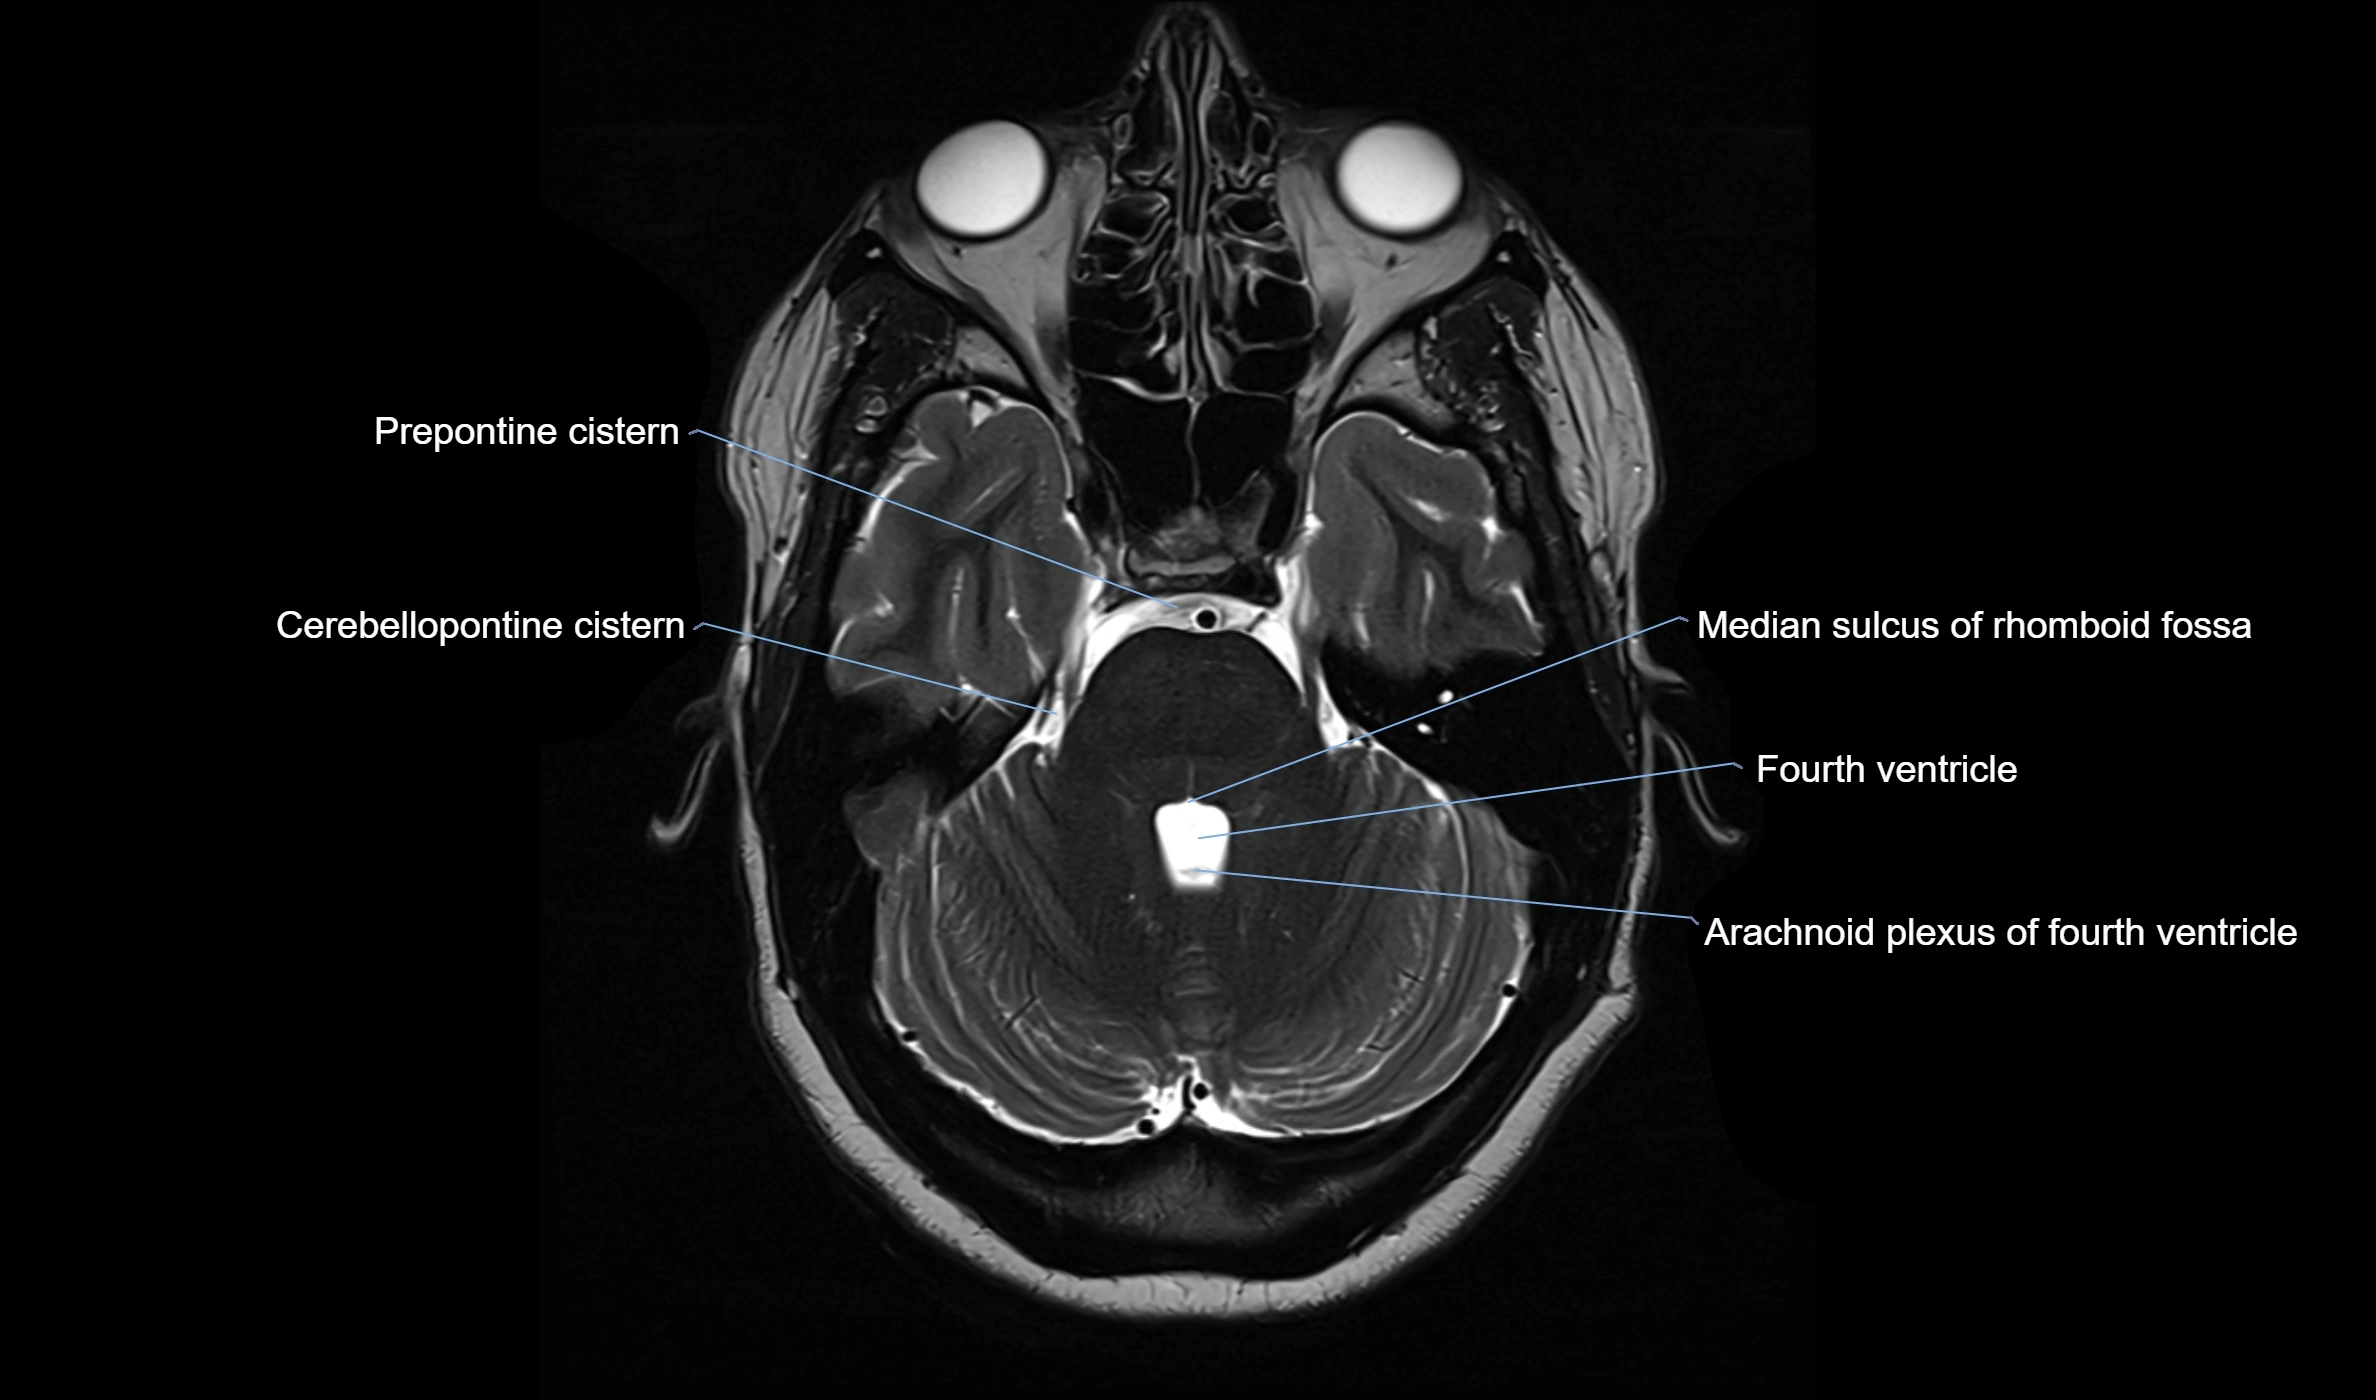

CT image

image